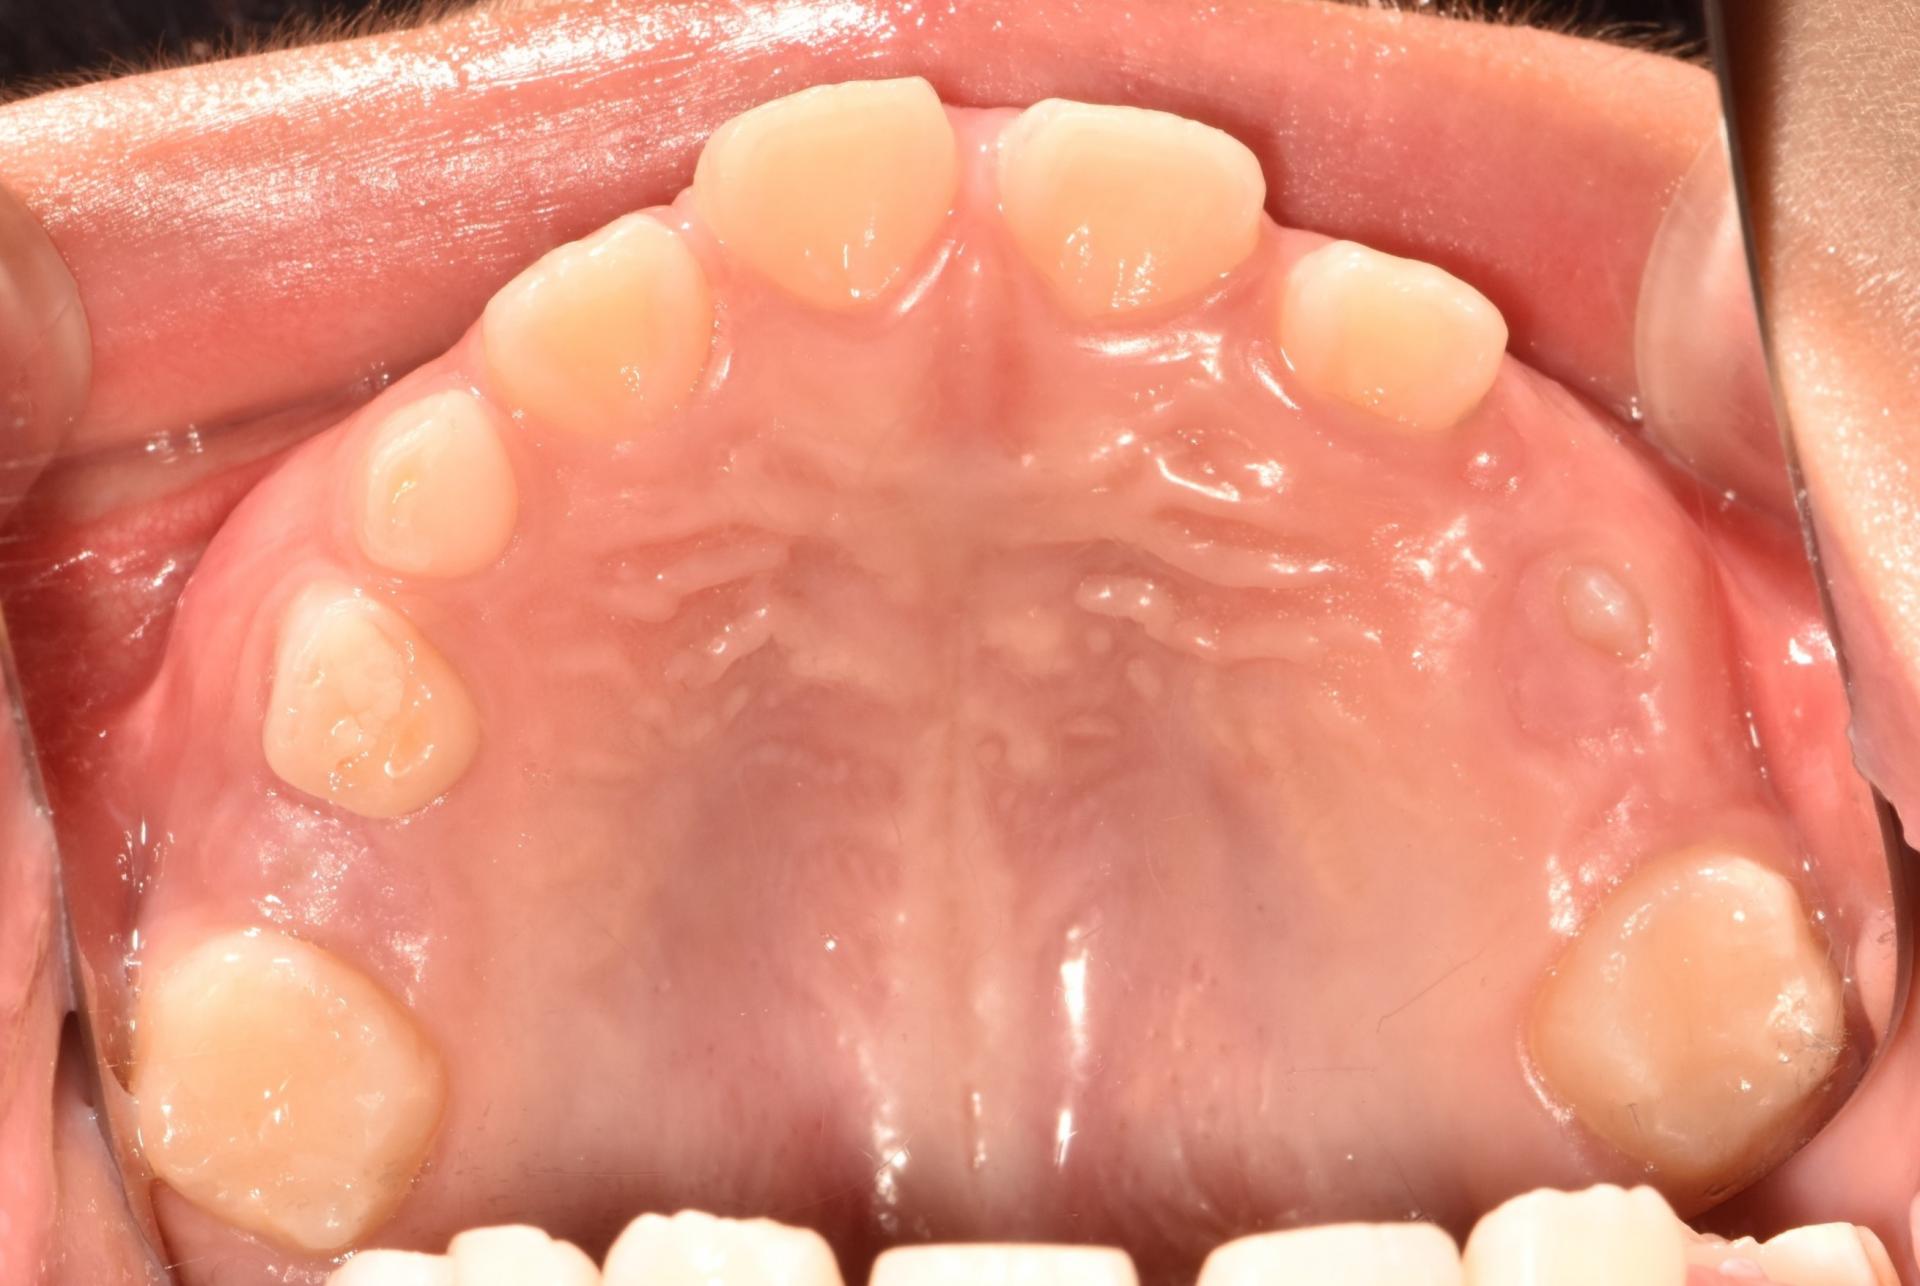

치료 전 구강 내 사진입니다 .

앞니가 벌어져 있고, 치아가 나올 공간이 부족합니다. 앞니끼리 서로 부딪히고 있네요.